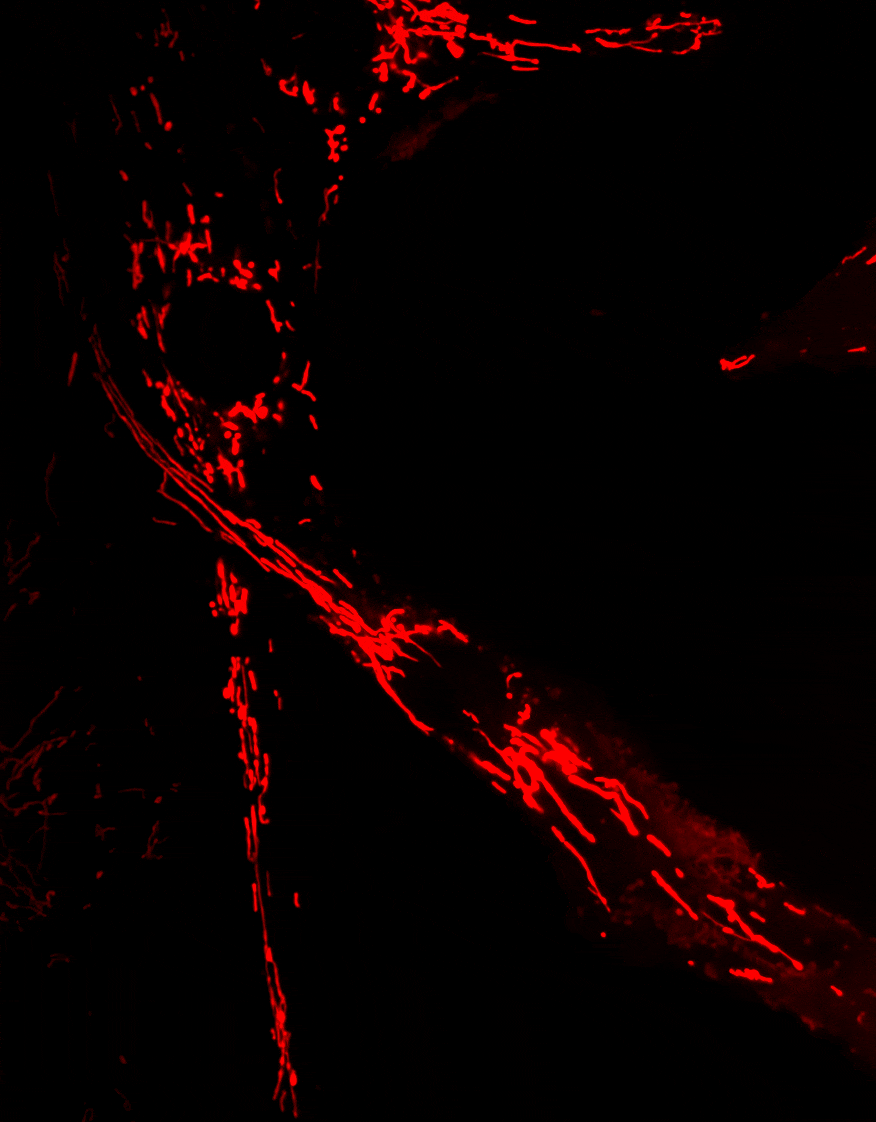

La mitophagie, un mécanisme essentiel permettant l’élimination des mitochondries endommagées, est altérée dans plusieurs maladies neurodégénératives. Des mutations du gène Optn ont été identifiées dans des pathologies telles que le glaucome et la sclérose latérale amyotrophique (SLA).

Nos travaux visent à comprendre le rôle d’OPTN dans le transport et l’élimination des mitochondries, et à déterminer comment les dysfonctionnements de ces processus contribuent au développement de maladies neurodégénératives.

Phosphorylation of Optineurin by protein kinase D regulates Parkin-dependent mitophagy. Weil R, Laplantine E, Attailia M, Oudin A, Curic S, Yokota A, Banide E, Génin P. iScience. 2024 Nov 13;27(12):111384. doi: 10.1016/j.isci.2024.111384. eCollection 2024 Dec 20. PMID: 39669425